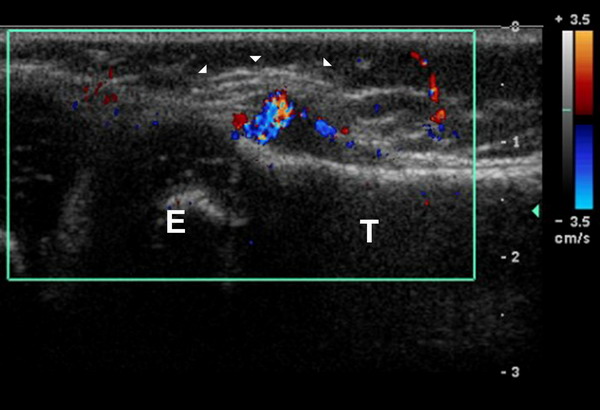

Figure 1: Grey Scale with Color Doppler Longitudinal

Ultrasound image demonstrates a hypoechoic pre-tibial soft

tissue lesion (white arrowheads) with central color flow (T –

tibial shaft, E – tibial epiphysis).

normal. This was followed by an ultrasound, which demonstrated

a hypoechoic, soft tissue mass with cortical destruction (figure

1). CT imaging demonstrated a 5mm eccentrically located lucent